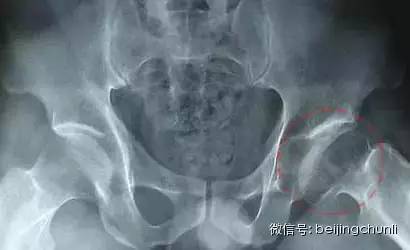

晚期: 股骨头骨结构完全消失,股骨头明显变扁或覃状变形,内有弥漫或局限性硬化或囊变区,关节间隙变窄,股骨头增粗,可有关节半脱位。髋臼缘和股骨头基底部增生变成骨赘,髋臼关节面出现硬化并囊变,股骨头与髋臼变扁,股骨颈吸收,使下肢变短。

股骨头坏死

上图为晚期可能大

Ⅳ期 关节软骨被完全破坏,关节间隙变窄,股骨头显著塌陷变形,髋臼出现硬化、囊性变及边缘骨赘等非特异性继发性骨关节炎。